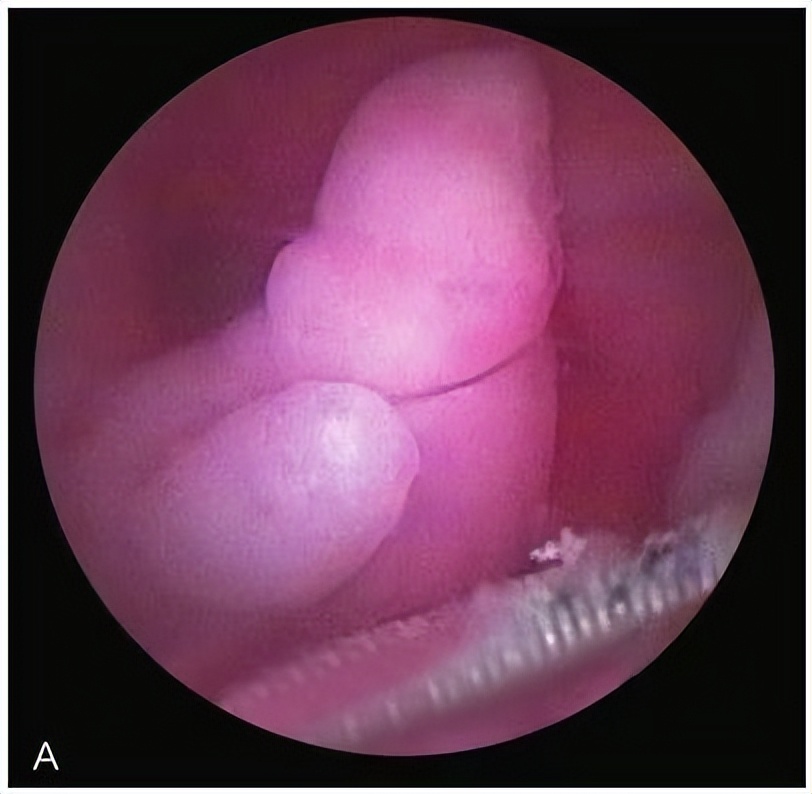

子宫内膜息肉及宫内节育器

子宫内膜息肉

子宫内膜多发息肉